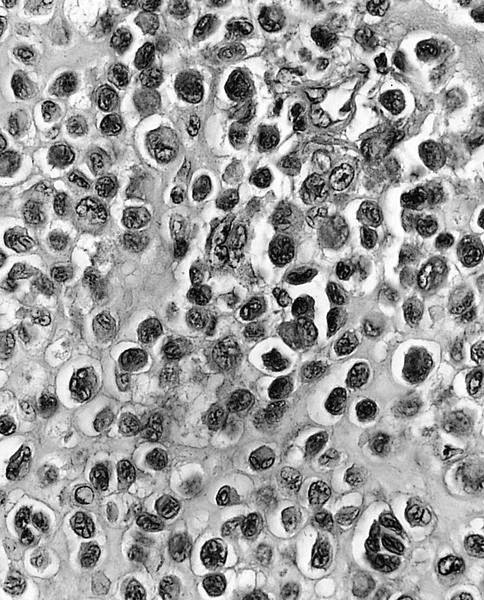

Electron microscopy description

- Resembles tissue culture epiphyseal cartilage cells with prominent fibrous lamina that causes microscopic well defined cell borders (Cancer 1972;30:401)